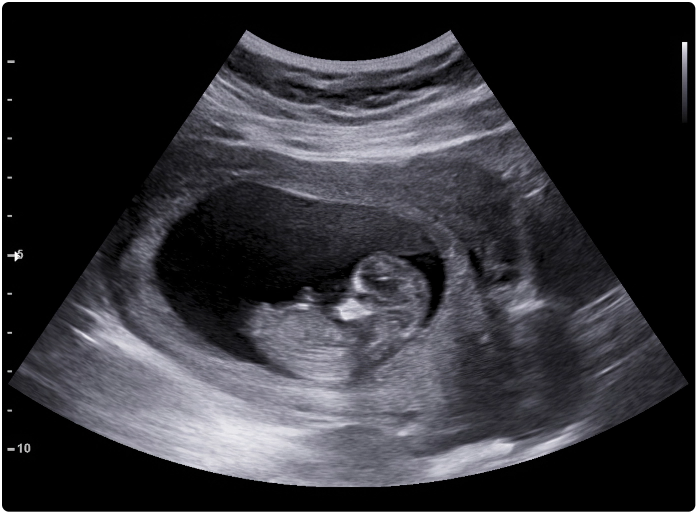

24 WEEKS

4DGrowth&Wellbeing™ Scan

Our 4DGrowth&Wellbeing™ scan is available from 24 to 32 weeks. Zoe and Antony’s first 4D scan took place when Zoe was 24 weeks along. Once again, they brought their families with them, and everyone was excited to see the little man’s face for the first time.

Antony described that first glimpse of his son’s face as “brilliant and surreal”. He also said that First Encounters “made a great experience even more memorable by creating such a relaxing atmosphere in the clinic”.

Luckily, the baby was perfectly positioned for his close-up, and the couple came home with some fantastic images of their little boy that they were extremely pleased with.